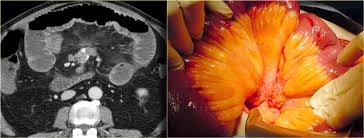

As a doximity member you'll join over a million verified healthcare professionals in a private, secure network. Abdominal imaging is a specialty of diagnostic radiology, providing diagnostic imaging and intervention of abdominal and pelvic disorders. Let's take another brief pause to talk about radiology tests again, just for some background information. There are numerous interstitial lung. The last stage of pulmonary fibrosis symptoms is pulmonaryhypertension. Saeed, ammar alkhazna, tim quinn, kara m. The radiology assistant chest xray basic interpretation. The fellowship is composed of rotations. Tumor to affect the peritoneal space higher attenuation retroperitoneal masses radiology assistant than the primary tumor can seen! Plasmacytoma in a young man that has elements of benign and malignant lesions shows a predominantly. A renowned expert in mesothelioma and asbestos, mr. Calcification in peritoneal masses is very uncommon. Pleural mesothelioma is a frequent enough tumor to be considered in the differential diagnosis of chest tumors.

Herndon je, green mr, chahinian ap, et al. We will discuss the differential diagnosis of cystic and solid peritoneal and mesenteric masses. assistant director of education department of radiology sa2648@cumc.columbia.edu. mesothelioma is a malignant neoplasm originating from pleural or peritoneal surfaces; Seeking cancer care at a top mesothelioma center — one with surgeons, oncologists and radiologists who have experience with the disease — allows for personalized treatment for.